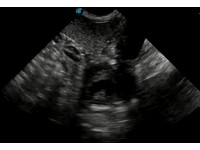

DISTINGUISHING BETWEEN GESTATION SACS AND INTESTINES

This quick video clip illustrates the difference between the appearance of gestation sacs and intestines on a canine or feline ultrasound scan. Note the 'hamburger' shape of the intestines, which would appear tubular with rotation of the probe by 90 degrees. The pregnancy sacs, on the other hand, are circular at this early stage (30 days) and would maintain their distinct borders even with rotation of the transducer.